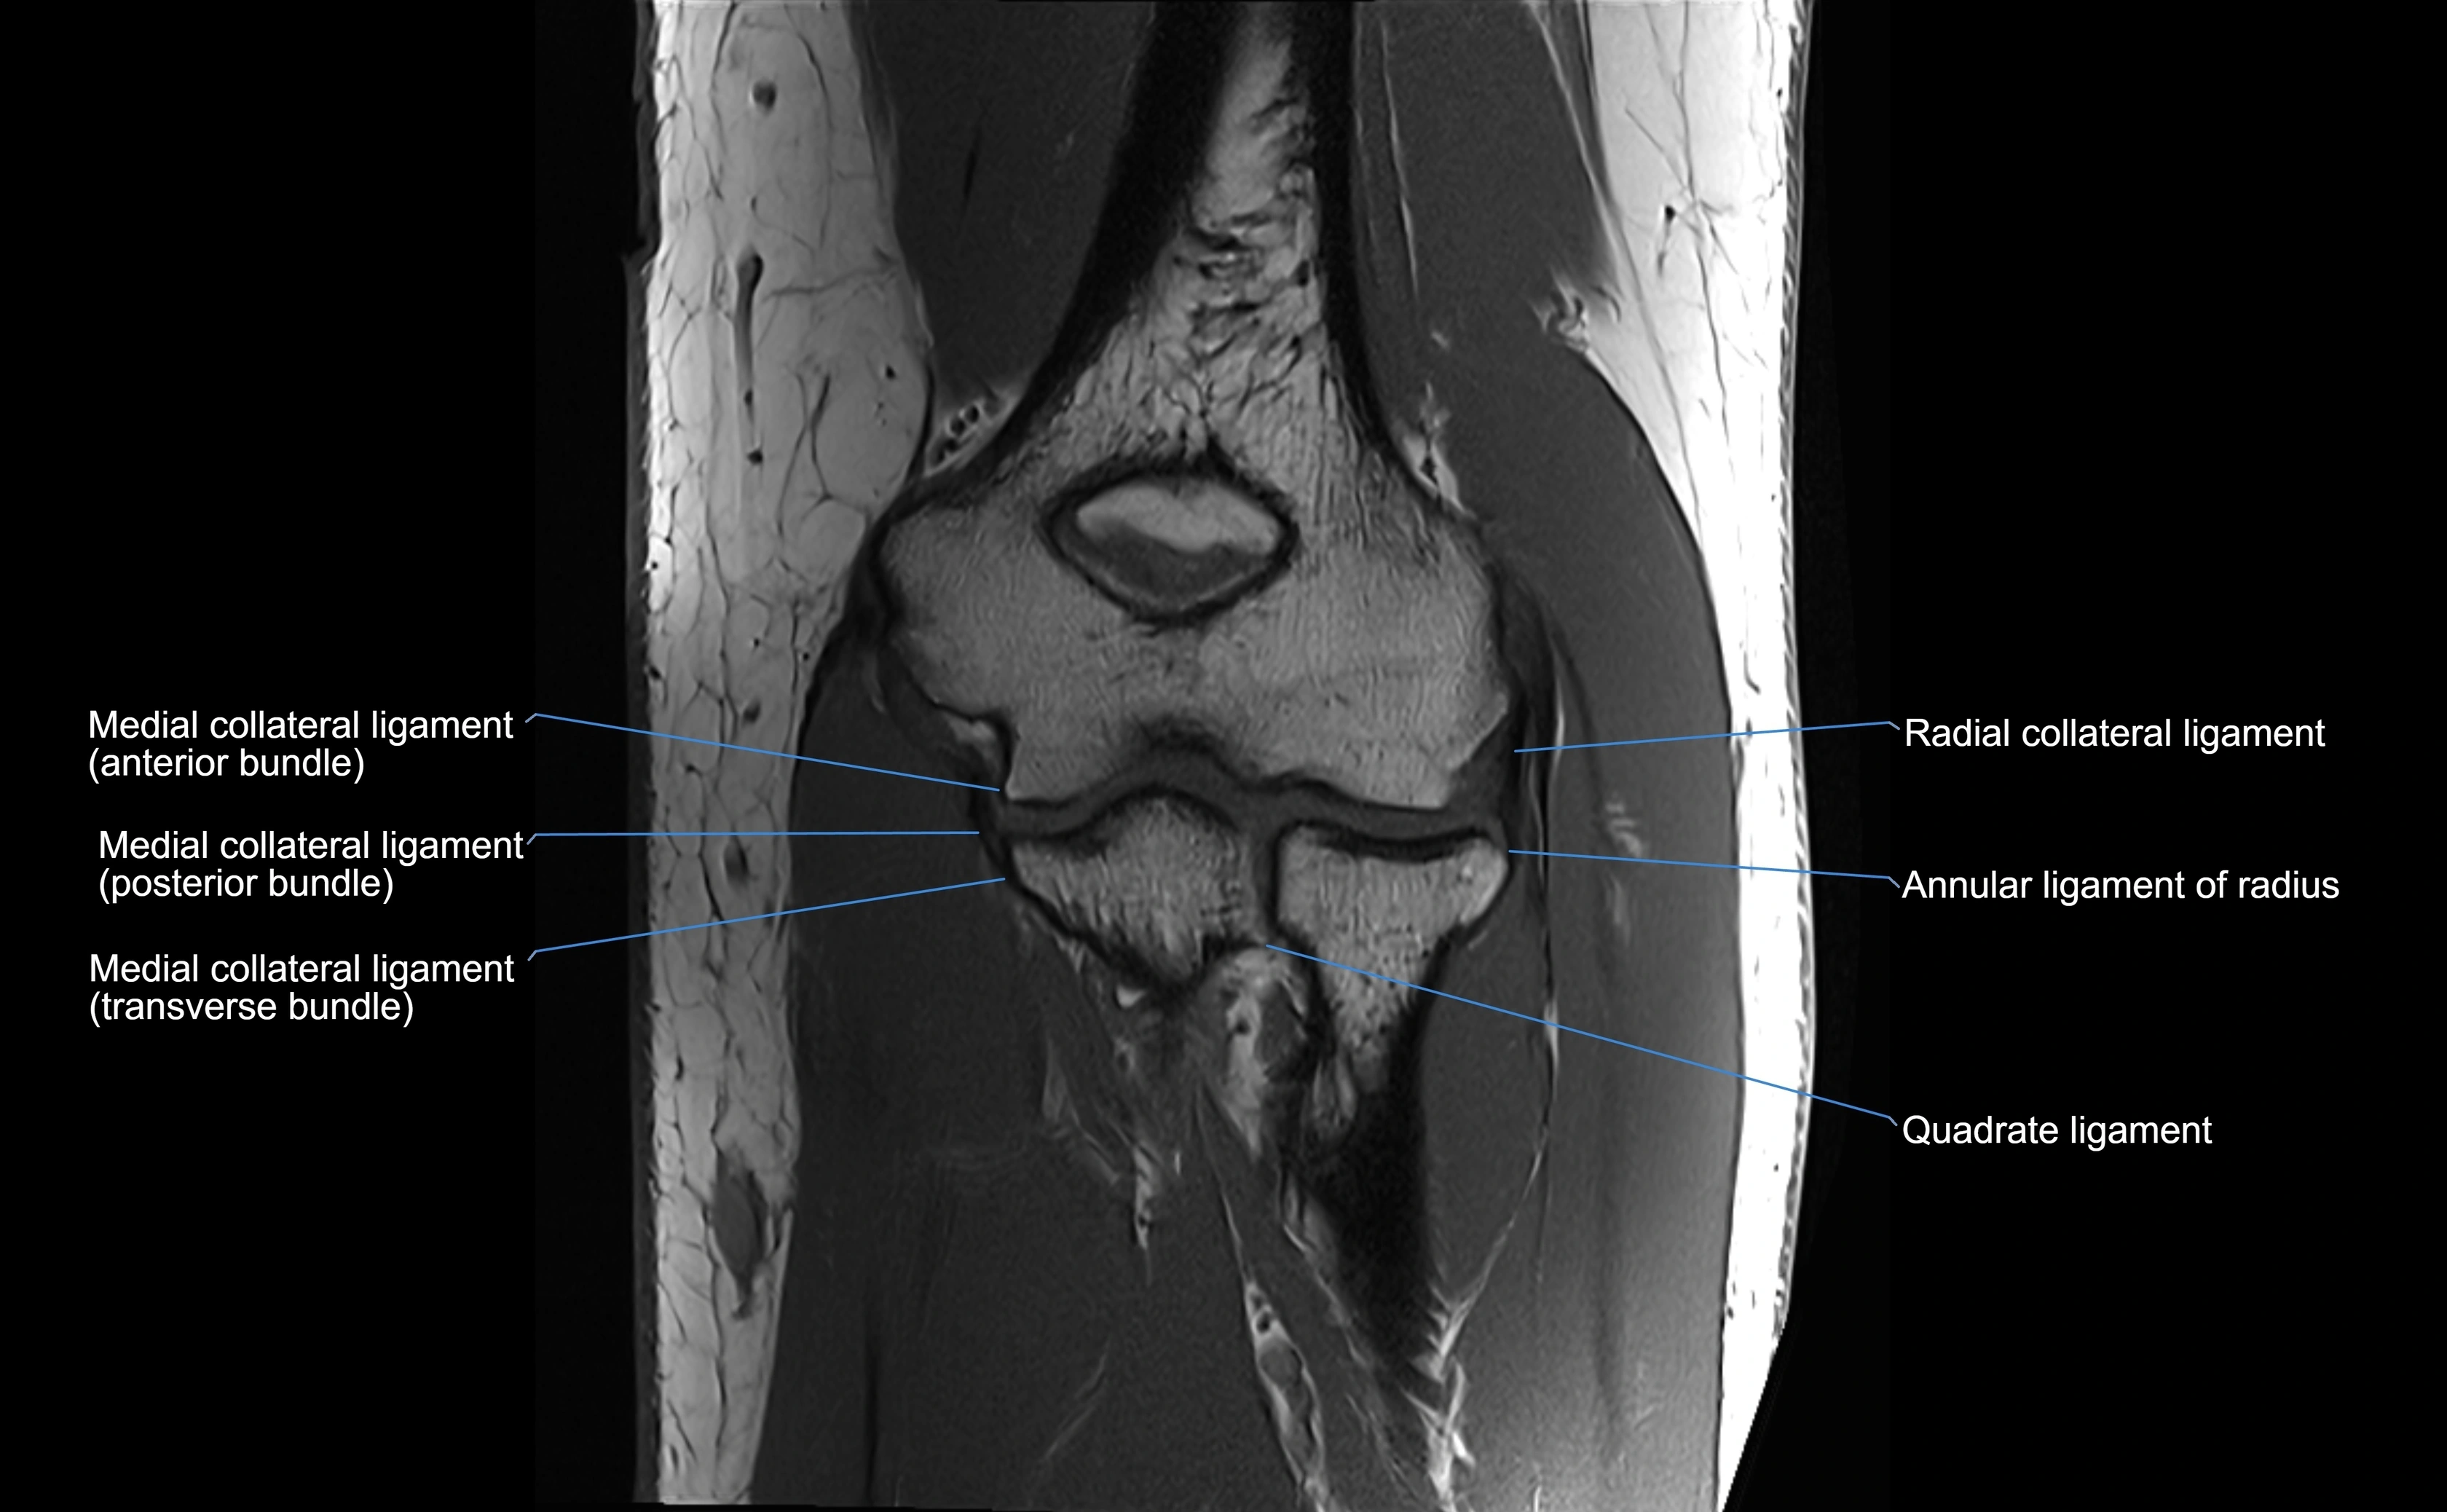

Annular ligament of radius

The annular ligament of the radius is a strong, circular band of fibers that encircles the head and neck of the radius, holding it securely against the radial notch of the ulna. It forms part of the proximal radioulnar joint, permitting smooth rotation of the radius during pronation and supination of the forearm.

The ligament acts like a collar or loop, maintaining radial head stability while allowing rotation. It is essential for forearm motion, elbow stability, and load transmission from the radius to the ulna and humerus.

Origin, Course, and Insertion

• Origin: Arises from the anterior margin of the radial notch of the ulna.

• Course: Forms a strong circular band that wraps around the radial head and neck, maintaining them within the radial notch.

• Insertion: Attaches to the posterior margin of the radial notch, completing a fibrous ring around the radial head.

• The inner surface of the ligament is lined with synovial membrane, allowing frictionless rotation.

Relations

• Superiorly: Blends with the capsule of the elbow joint.

• Inferiorly: Supported by the quadrate ligament at the neck of the radius.

• Medially: Attached to the ulnar radial notch.

• Laterally: In contact with the radial head and its articular cartilage.

• Anteriorly: Related to the radial collateral ligament of the elbow.

• Posteriorly: Continuous with the elbow joint capsule.